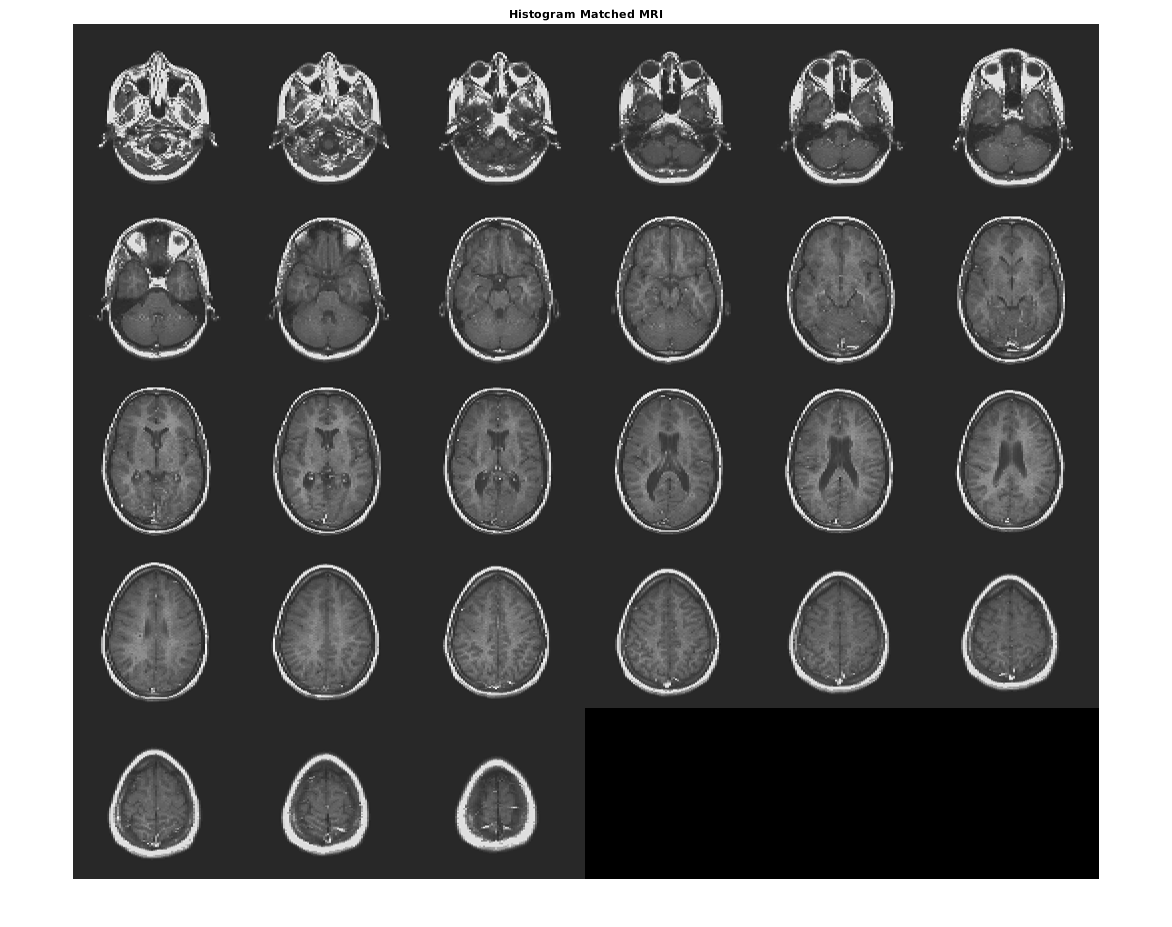

Совпадайте с гистограммой D к гистограмме полноразмерного ref.

Dmatched = imhistmatchn(D,ref);

Отобразите вывод. Заметьте, что уровни яркости выхода более тесно совпадают со ссылочным изображением, чем оригинальное изображение.

figure

montage(Dmatched,'DisplayRange',[])

title('Histogram Matched MRI')